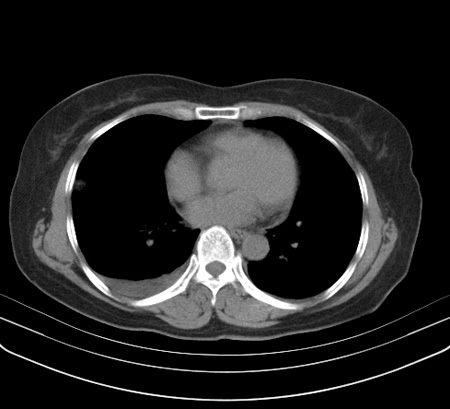

以下是引用余辉在2009-2-19 20:10:00的发言:[br]多考虑急性感染性病变,右中叶尚可见多枚小斑片状影,多为化脓性肺炎,双侧胸腔积液

以下是引用随光逐影在2009-2-19 20:33:00的发言:[br]1)考虑右肺炎症;建议抗炎治疗后复查。2)双侧胸腔积液(以右侧为甚)。

以下是引用花凤凰在2009-2-19 20:46:00的发言:[br]病人有发热,胸痛急性起病,主要病变位于右肺中叶外侧段,呈楔行改变,位于外带胸膜下,考虑为肺梗塞可能!!!!!!!!!!!!!!!!!!!!!!!!!!!!!!!!!!!